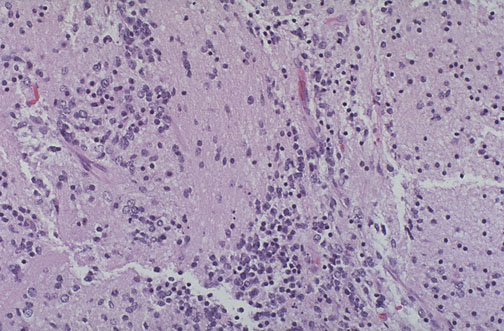

| A teratoma is judged to be "immature" with a variable propensity for malignant biologic behavior when there are primitive embryologic elements present. These are neuroectodermal elements, seen here as primitive neural cells (the larger blue ones looking like neuroblasts) with a neuropil background. The more such elements, the higher the grade. |